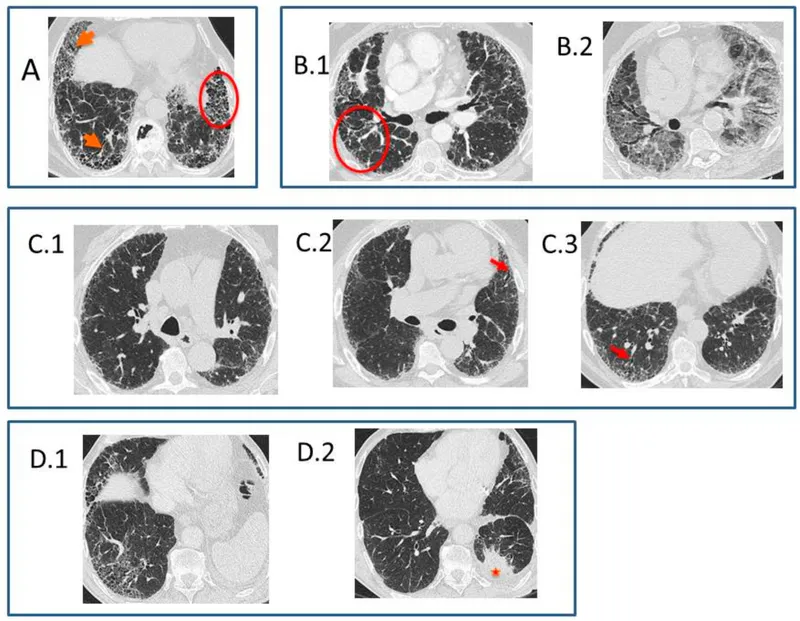

- Gross/CT: Honeycomb lung (esp. subpleural, basal).

- Diagnosis: HRCT (typical UIP: subpleural, basal predominant reticulation, honeycombing, traction bronchiectasis). Biopsy if HRCT atypical.

- IPF: Usual Interstitial Pneumonia (UIP) pattern, honeycomb lung on HRCT.